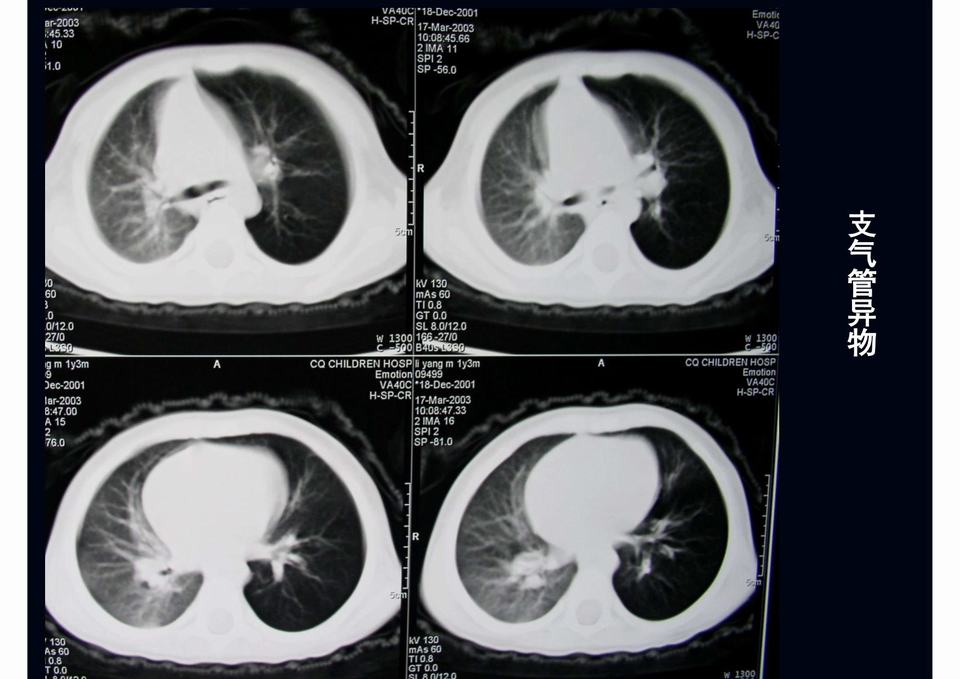

图01